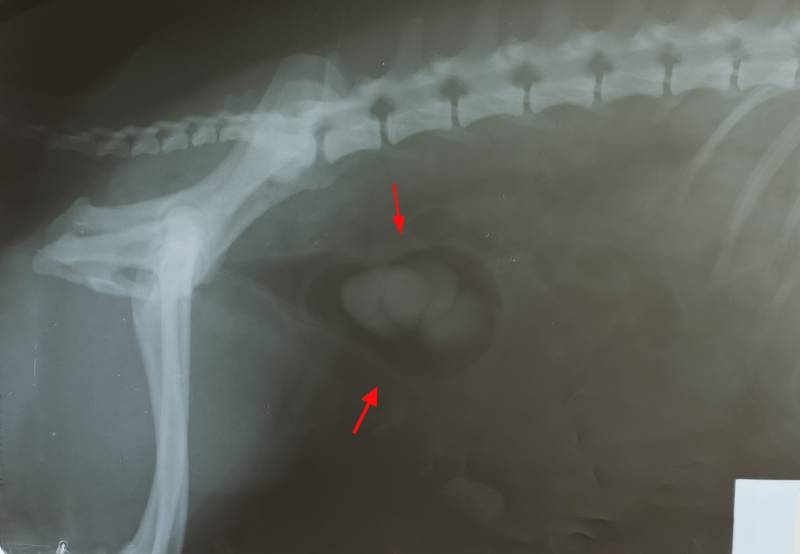

As previously mentioned, kidney stones are often only diagnosed as an incidental finding when radiographs are taken of the abdomen, sometimes for a problem that is completely unrelated! In these cases, the presence of the stones is noted, but treatment is not necessarily needed.

Most kidney or bladder stones are visible on X-rays but some will not show up on a normal X-ray. If stones are suspected, your vet may perform additional imaging tests such as ultrasound or X-rays with air or contrast material in the bladder to highlight stones that do not show up on plain X-rays.

Imaging is a vital part of the diagnostic process in order to distinguish between stones or other urogenital problems such as bladder cancer, prostate disease in male dogs, or infection of the uterus (pyometra) in non-spayed female dogs. It will also help determine how the stone should be treated.